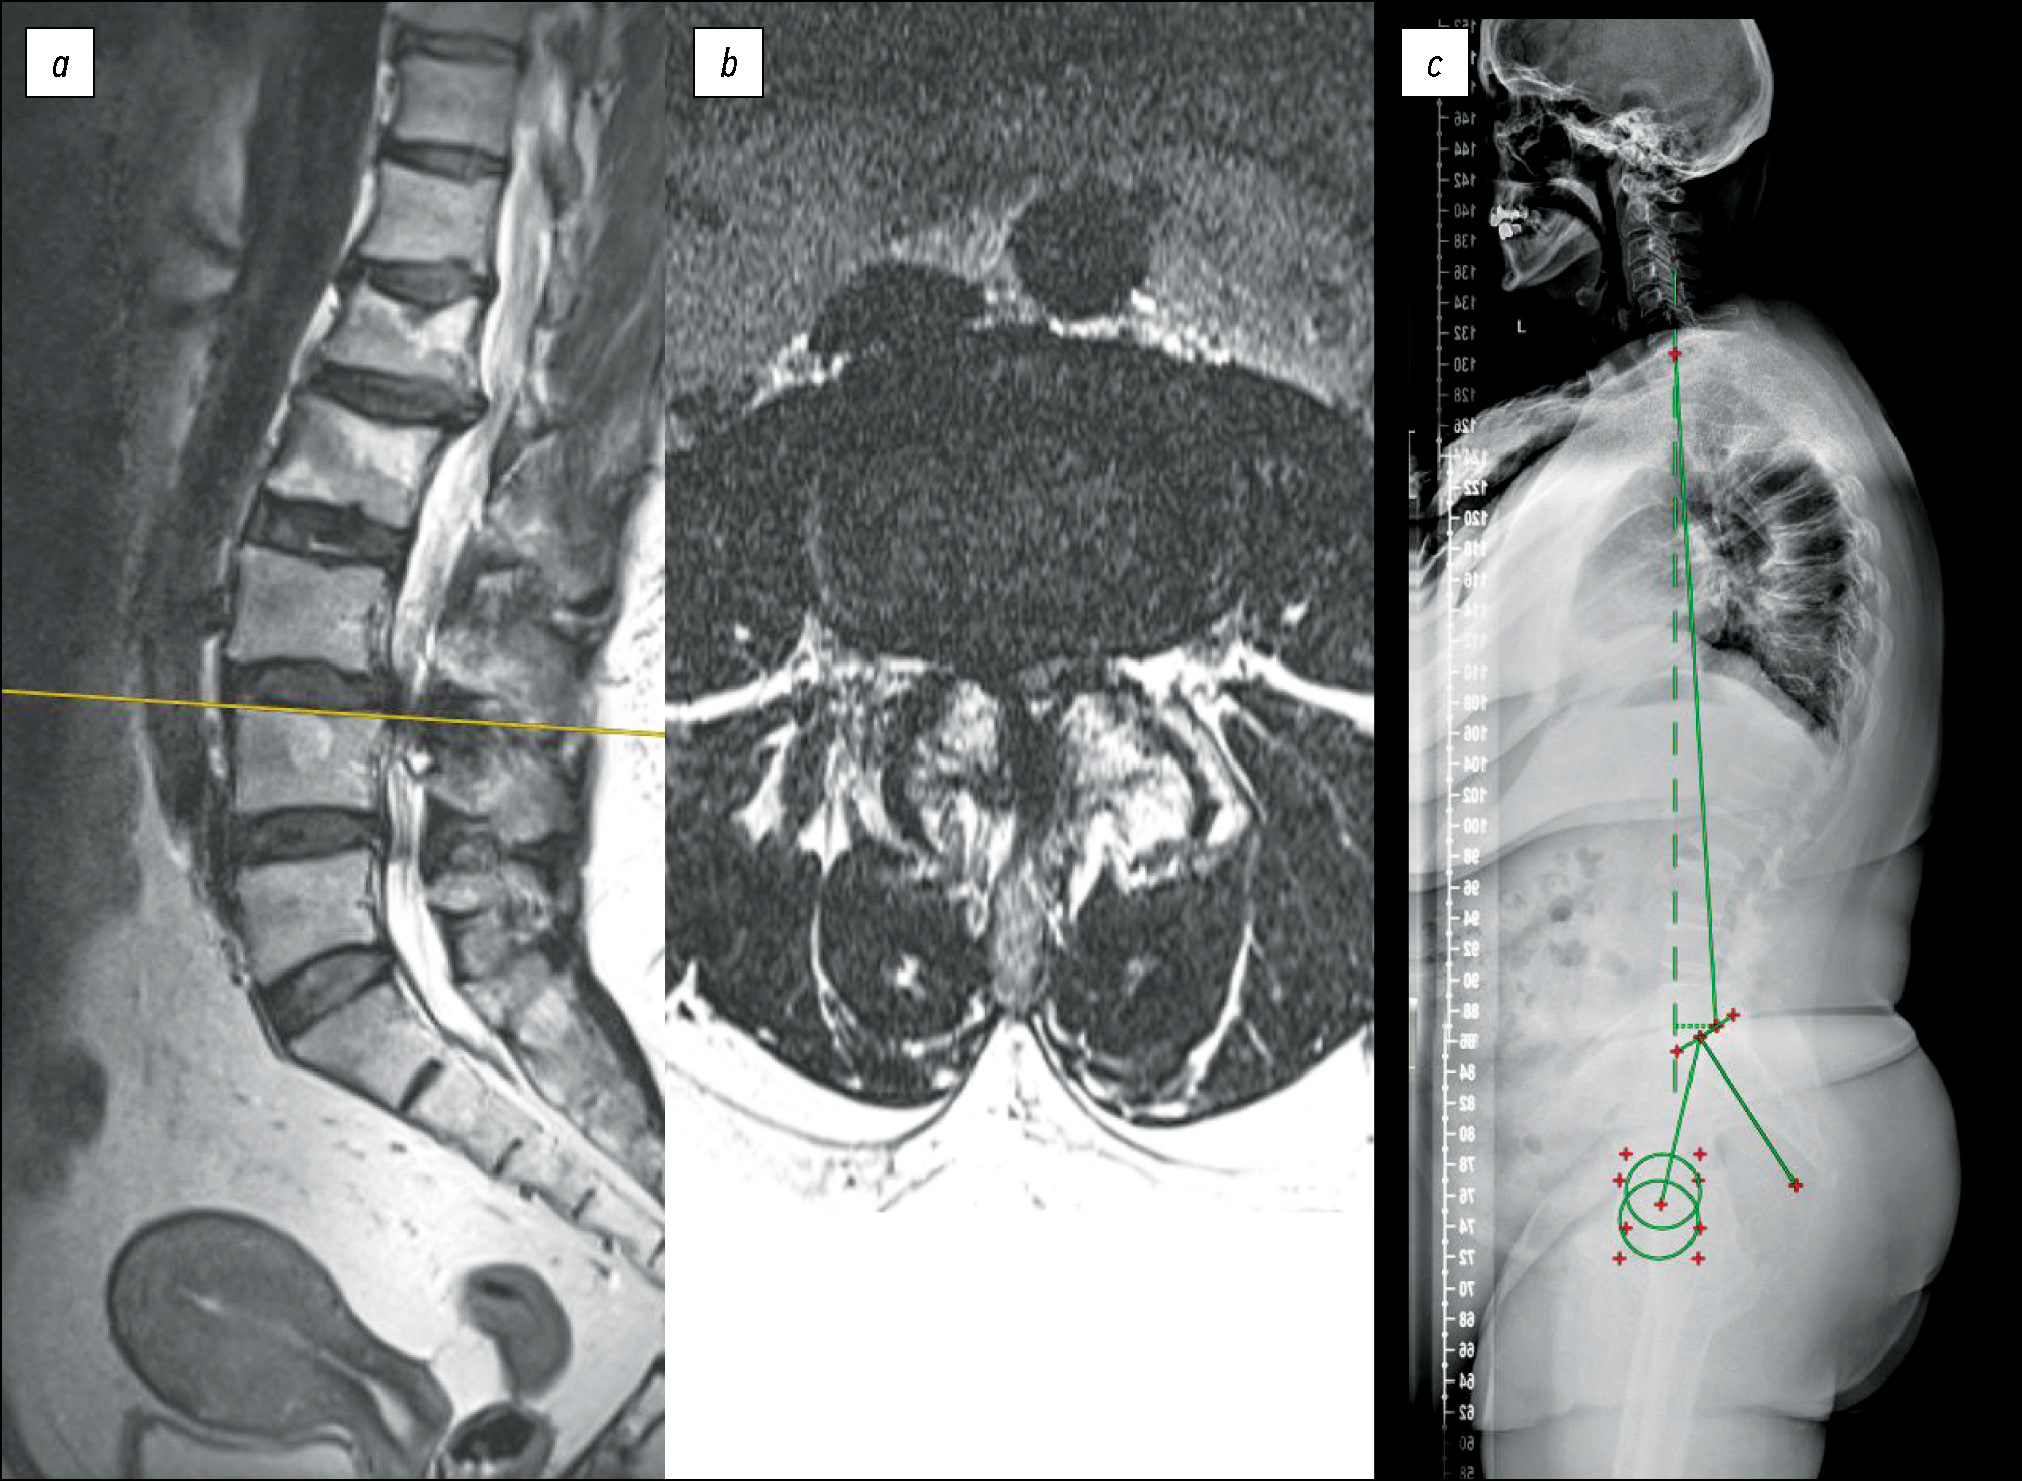

Рис. 2. Пациентка И., 62 года: ВАШ спины — 4 балла, ВАШ ноги — 5 баллов, ODI=64,44%, DN4 до операции — 7 баллов; a, b — МРТ поясничного отдела позвоночника — дегенеративный стеноз на уровне L3-L4 степени С по Schizas; с — постуральная рентгенография позвоночника — индекс Barrey=0,71. Хирургическое лечение — микрохирургическая декомпрессия «over-the-top» на уровне L3-L4. Несмотря на достигнутую рекалибрацию до степени B по Schizas, у пациентки сохраняются боли в нижних конечностях. ODI — 48,89%, ВАШ ноги — 4 балла, ВАШ спины — 3 балла. Клинически успех достигнут — регресс по ODI на 15,5%, достигнута рекалибрация позвоночного канала, однако пациентка результатом оперативного лечения не удовлетворена — 3 по шкале Ликерта («состояние без изменений»). Сохраняется высокое значение нейропатической боли: DN4=7 баллов. Хирургическое лечение признано неуспешным.